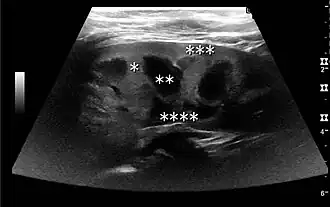

The kidney is divided into parenchyma and renal sinus. The renal sinus is hyperechoic and is composed of calyces, the renal pelvis, fat and the major intrarenal vessels. In the normal kidney, the urinary collecting system in the renal sinus is not visible, but it creates a heteroechoic appearance with the interposed fat and vessels. The parenchyma is more hypoechoic and homogenous and is divided into the outermost cortex and the innermost and slightly less echogenic medullary pyramids. Between the pyramids are the cortical infoldings, called columns of Bertin (Figure 1). In the pediatric patient, it is easier to differentiate the hypoechoic medullar pyramids from the more echogenic peripheral zone of the cortex in the parenchyma rim, as well as the columns of Bertin (Figure 2).[1]

Figure 1. Normal adult kidney. Measurement of kidney length on the US image is illustrated by '+' and a dashed line. *Column of Bertin; ** pyramid; *** cortex; **** sinus.[1]